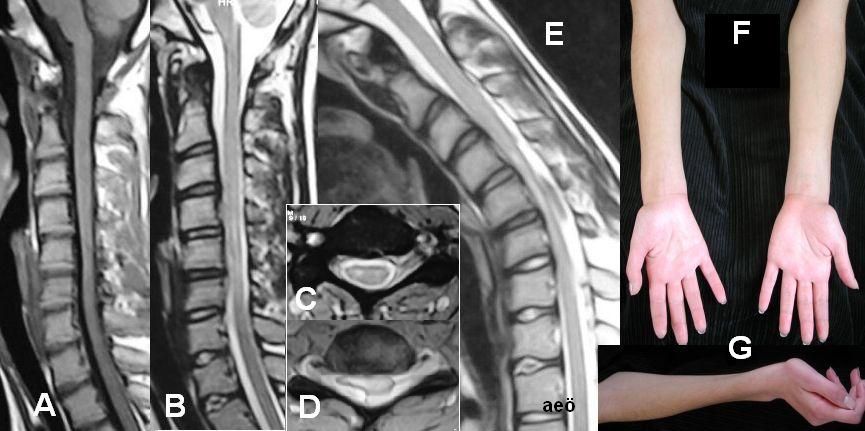

Miyelit teşhisinde hangi testler kullanılmaktadır?

Miyelitte en önemli inceleme yöntemi omurilik MR'ı ve beyin omurilik sıvısının (BOS) analizidir. Omurilik iltihabı MR'da görüntülendikten sonra öncelikle iltihabın altında yatabilecek olan bir mikrobun olup olmadığına bakılması gerekmektedir. Bu durumda kan incelemeleri, akciğer grafisi ve BOS incelemeleri gibi incelemelerin yapılması gerekebilir.

Miyelit teşhisinde hangi testler kullanılmaktadır?

Miyelitte en önemli inceleme yöntemi omurilik MR'ı ve beyin omurilik sıvısının (BOS) analizidir. Omurilik iltihabı MR'da görüntülendikten sonra öncelikle iltihabın altında yatabilecek olan bir mikrobun olup olmadığına bakılması gerekmektedir. Bu durumda kan incelemeleri, akciğer grafisi ve BOS incelemeleri gibi incelemelerin yapılması gerekebilir.